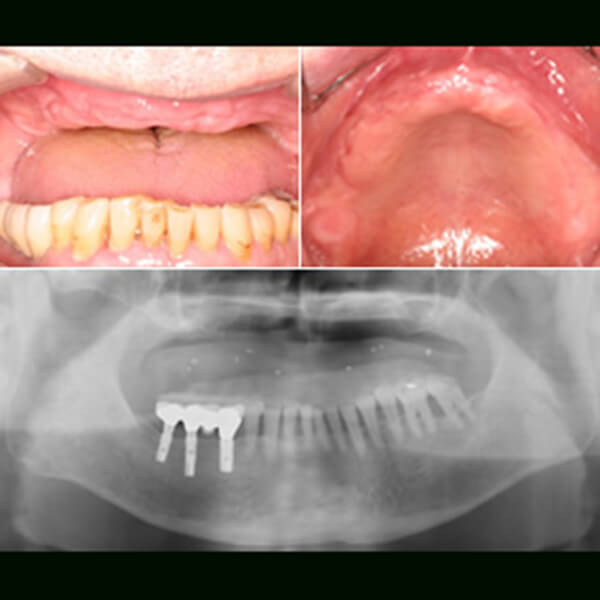

治療例②:

骨幅が少ない部分に

GBRを用いた例

インプラントを埋入予定

左側3本のインプラントを埋入予定。

インプラントを埋入

インプラントを埋入してチタンの土台をとりつけました。

かぶせものをセット

最終のかぶせものがセットされました。

インプラント埋入後

インプラント埋入後のレントゲン写真。